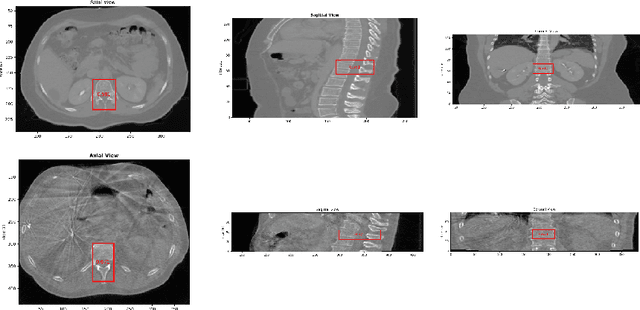

Abstract:Accurate matching of pedicle screws in both anteroposterior (AP) and lateral (LAT) images is critical for successful spinal decompression and stabilization during surgery. However, establishing screw correspondence, especially in LAT views, remains a significant clinical challenge. This paper introduces a method to address pedicle screw correspondence and pose estimation from dual C-arm images. By comparing screw combinations, the approach demonstrates consistent accuracy in both pairing and registration tasks. The method also employs 2D-3D alignment with screw CAD 3D models to accurately pair and estimate screw pose from dual views. Our results show that the correct screw combination consistently outperforms incorrect pairings across all test cases, even prior to registration. After registration, the correct combination further enhances alignment between projections and images, significantly reducing projection error. This approach shows promise for improving surgical outcomes in spinal procedures by providing reliable feedback on screw positioning.